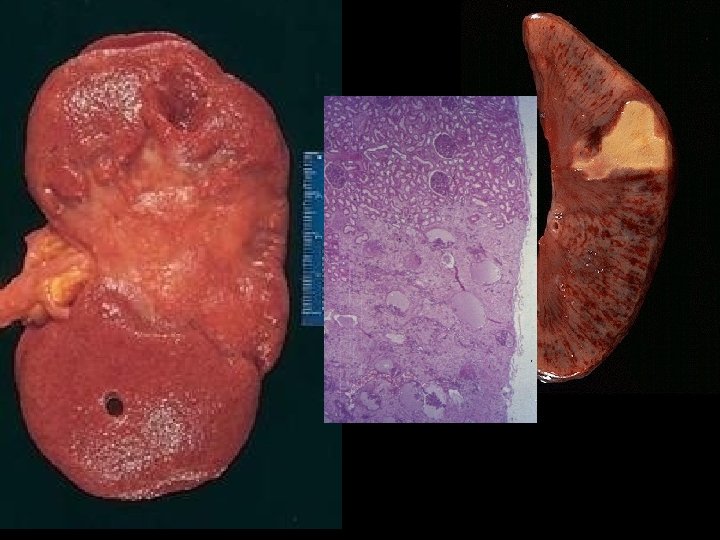

Acute Passive Congestion, Liver

CHRONIC PASSIVE HYPEREMIA/CONGESTION, LIVER

PATHOLOGY • • MULTIPLE ORGAN FAILURE SUBENDOCARDIAL HEMORRHAGE (why? ) ACUTE TUBULAR NECROSIS (why? ) DAD (Diffuse Alveolar Damage, lung) (why? ) GI MUCOSAL HEMORRHAGES (why? ) LIVER NECROSIS (why? ) DIC (why? )

ATN